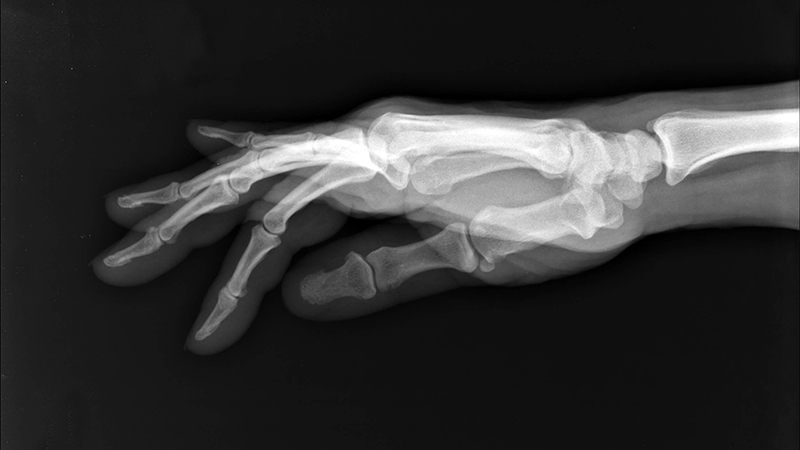

Roentgen reconoció inmediatamente que había descubierto algo completamente nuevo. Durante las siguientes siete semanas se dedicó obsesivamente a investigar las propiedades de estos rayos misteriosos. Le confesó a su esposa: “Estoy haciendo algo que hará que la gente, cuando se entere, diga: “Roentgen ha perdido la cabeza””. El 22 de diciembre de 1895, realizó la primera radiografía humana que fue la mano de su esposa Anna Bertha Ludwig, revelando con asombroso detalle los huesos y el anillo de bodas.